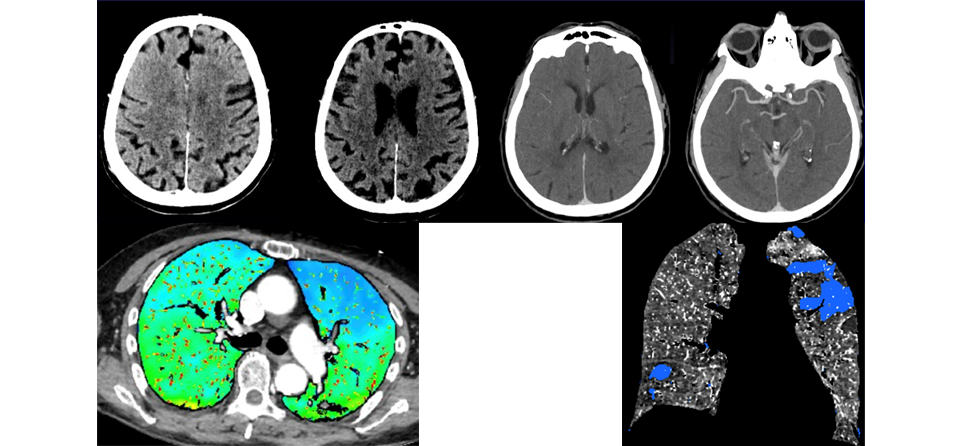

Patiente de 82 ans, sans ATCD particulier, vit seule à domicile, autonome.

Retrouvée dans le coma à domicile. Service Réa appelle pour diagnostic étiologique avant tout résultat biologique.

TDM crâne – et + iv, thorax Abdomen Pelvien au temps portal, scanner spectral.

======== Scanner cérébral ========

Pas de signes d'HTIC.

Pas d'AVC ischémique ou hémorragique.

Atrophie avec leucoaréiose banale.

Pas d'oedème intra-cérébral.

Pas de prise de contraste focale anomale.